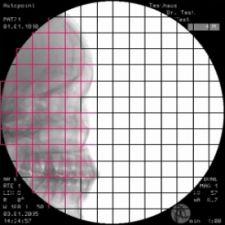

Ziehm’s Object Detected Dose Control feature for the Vision line of C-arms purportedly improves image quality with a low dose while also making the system easier to handle. The new real-time image control covers the whole field of view and provides independent object positioning within the field.

The tool allows real-time motion detection, which adjusts the noise reduction level whenever there are moving objects. The system also reduces the pulse frequency in the case of non-moving objects. The new tool also features automatic metal correction to reduce the blooming effect, to produce optimal image quality even when there is metal in the image.